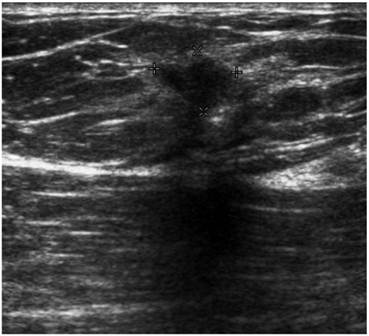

Mucinous Carcinoma With Axillary Lymph Node Metastasis In A ...

2. Dragoumis DM, Assimaki AS, Tsiftsoglou AP. Pure mucinous carcinoma with axillary lymph node metastasis in a male breast. Breast Cancer 2009 Sep ... Read More

Breast ultrasound And New Technologies - Ejradiology.com

Breast ultrasound and new technologies Giorgio Rizzatto *, Roberta Chersevani In this case of carcinoma of the male breast vascularity is artifactually absent after the first centimetre. G. Rizzatto, R. Cherse6ani:European Journal of Radiology 27 (1998)S242 ... Access This Document

Pt1: Breast Ultrasound L breast transverse view L breast transverse view . Ultrasound-guided core biopsy. PACS, BIDMC. • 70 y/o male p/w R breast periareolar thickening with nipple retraction. • FNA performed. • Pt referred for MG, US, and US-guided core ... Retrieve Doc